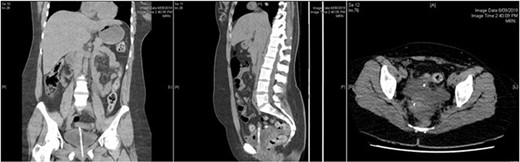

The patient proceeded to have a computed tomography (CT) of her abdomen, which could not suggest any reason for her symptoms. However, she did not improve clinically, and thus, we organized an ultrasound of the abdomen and pelvis to rule out any biliary pathology that could have been missed with CT scan (Fig. 1).

Abdominal CT showing urinary catheter protruding through dome of bladder.

The patient then underwent a laparoscopy, which confirmed a bladder dome perforation with the tip of the Foley’s catheter. Her pelvic organs appeared normal. Incidentally, violin-like liver adhesions were found during her laparoscopy in keeping with Fitz-Hugh–Curtis syndrome (FHCS). The bladder dome was repaired laparoscopically, and peritoneal fluid was sent for microscopy and culture. Retrospective re-evaluation of CT images confirmed the diagnosis (Figs 2 and 3).